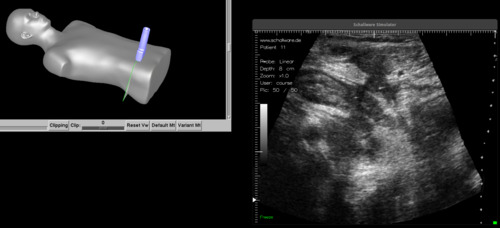

Der Aufbaukurs Pädiatrie wird während der Vortragsreihe an Simulatorarbeitsplätzen mit Puppe und Dummy-Sonde und mit den praktischen Übungen an Probanden und Ultraschallgeräten ausgeführt.

Die Vortragsreihe beinhaltet Vortraege, die unterbrochen werden mit interaktiven Übungen am Simulator mit Zugriff auf eine Pathologiedatenbank.

Arbeitsplatz Simulator Einzelplatz